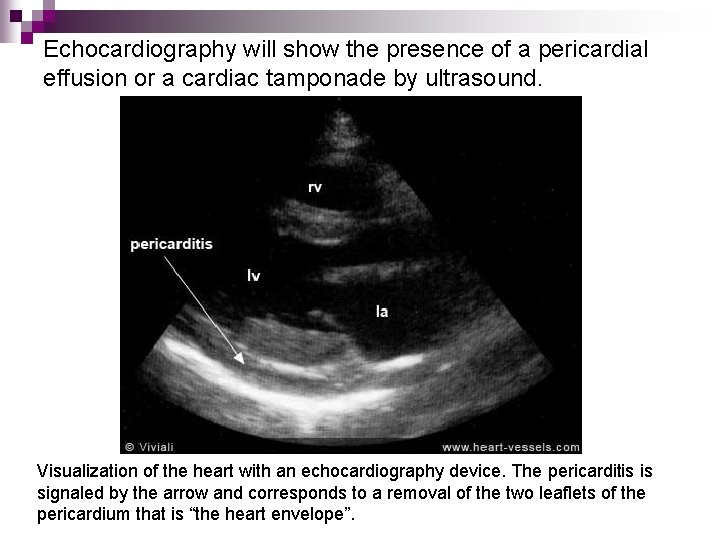

Echocardiography will show the presence of a pericardial effusion or a cardiac tamponade by ultrasound. Visualization of the heart with an echocardiography device. The pericarditis is signaled by the arrow and corresponds to a removal of the two leaflets of the pericardium that is “the heart envelope”.